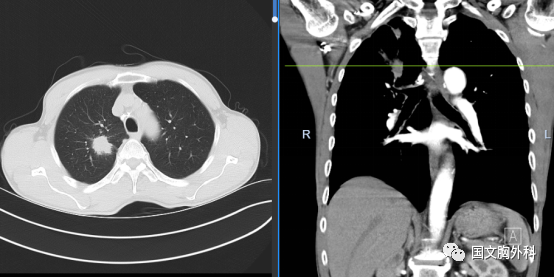

周大爺,發(fā)現(xiàn)肺占位1個(gè)月。CT下觀察右肺上葉腫物延續(xù)至肺門,穿刺病理提示:肺鱗癌。有手術(shù)機(jī)會(huì),家屬同意手術(shù)治療。